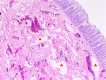

The aim of this study was to identify the frequency of rectosigmoidal involvement in patients with venous malformations (VM) of the lower extremities and to demonstrate multidisciplinary therapeutic options. The medical records and magnetic resonance images (MRI) of patients with VM of the lower extremities, over a six-year period, were reviewed retrospectively in order to determine the occurrence of rectosigmoidal involvement. Vascular interventions, surgical treatments, percutaneous and hybrid (endoscopy-guided angiography) sclerotherapy and procedural complications (according to Clavien-Dindo classification) were also noted. Of the 378 patients with vascular malformation of the lower limbs, 19 patients (5%) had documented venous rectosigmoidal malformation. All of these 19 patients reported episodes of rectal bleeding, while seven patients (36.8%) also had anemia. All patients underwent endoscopy. By endoscopy, seven patients (36.8%) showed discreet changes, and 12 patients (63.2%) showed pronounced signs of submucosal VM with active (47.3%) or previous (15.7%) bleeding. Treatment was performed in all patients with pronounced findings. Six patients underwent endoscopy-guided hybrid sclerotherapy, one patient underwent endoscopic tissue removal, one patient received percutaneous sclerotherapy and one patient received a combination of transvenous embolization and hybrid sclerotherapy. Three patients required open surgery. No complications occurred after conservative treatments; however, one complication was reported after open surgery. None of the treated patients reported further bleeding and anemia at the end of the follow-up period. In this cohort, rectosigmoidal VM occurred in 5% of patients presenting with a high incidence of rectal bleeding. Percutaneous or endoscopy-guided hybrid sclerotherapy appeared to be a safe and effective alternative to surgery.